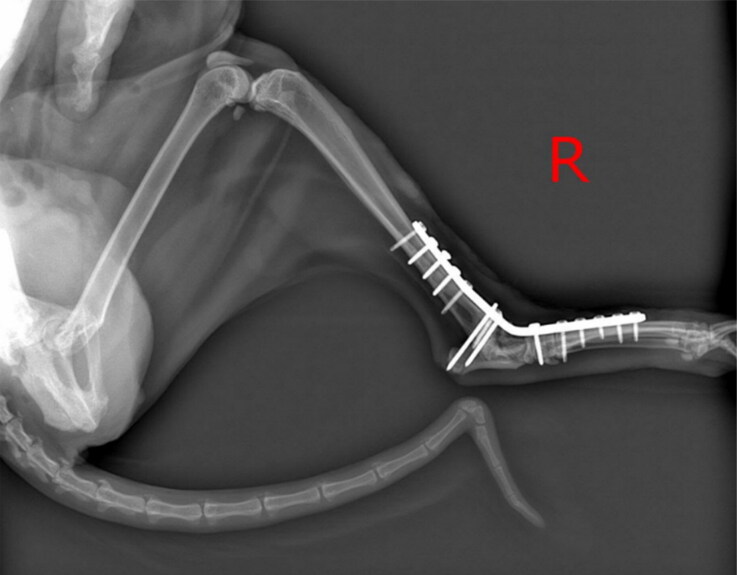

{"title":"用噬菌体抗生素成功治疗了一只暹罗猫的铜绿假单胞菌植入相关感染。","authors":"Ron Braunstein, Goran Hubanic, Ortal Yerushalmy, Sivan Oren-Alkalay, Amit Rimon, Shunit Coppenhagen-Glazer, Ofir Niv, Hilik Marom, Alin Barsheshet, Ronen Hazan","doi":"10.1080/01652176.2024.2350661","DOIUrl":null,"url":null,"abstract":"<p><p>Antibiotic-resistant pathogens are a growing global issue, leading to untreatable infectious diseases in both humans and animals. Personalized bacteriophage (phage) therapy, the use of specific anti-bacterial viruses, is currently a leading approach to combat antibiotic-resistant infections. The implementation of phage therapy has primarily been focused on humans, almost neglecting the impact of such infections on the health and welfare of companion animals. Pets also have the potential to spread resistant infections to their owners or the veterinary staff through zoonotic transmission. Here, we showcase personalized phage-antibiotic treatment of a cat with a multidrug-resistant <i>Pseudomonas aeruginosa</i> implant-associated infection post-arthrodesis surgery. The treatment encompassed a tailored combination of an anti-<i>P. aeruginosa</i> phage and ceftazidime, precisely matched to the pathogen. The phage was topically applied to the surgical wound while the antibiotic was administered intramuscularly. After two treatment courses spanning 7 and 3 weeks, the surgical wound, which had previously remained open for five months, fully closed. To the best of our knowledge, this is the first case of personalized phage therapy application in felines, which provides further evidence of the effectiveness of this approach. The successful outcome paves the way for personalized phage-antibiotic treatments against persistent infections therapy in veterinary practice.</p>","PeriodicalId":51207,"journal":{"name":"Veterinary Quarterly","volume":"44 1","pages":"1-9"},"PeriodicalIF":5.2000,"publicationDate":"2024-12-01","publicationTypes":"Journal Article","fieldsOfStudy":null,"isOpenAccess":false,"openAccessPdf":"https://www.ncbi.nlm.nih.gov/pmc/articles/PMC11089911/pdf/","citationCount":"0","resultStr":"{\"title\":\"Successful phage-antibiotic therapy of <i>P. aeruginosa</i> implant-associated infection in a Siamese cat.\",\"authors\":\"Ron Braunstein, Goran Hubanic, Ortal Yerushalmy, Sivan Oren-Alkalay, Amit Rimon, Shunit Coppenhagen-Glazer, Ofir Niv, Hilik Marom, Alin Barsheshet, Ronen Hazan\",\"doi\":\"10.1080/01652176.2024.2350661\",\"DOIUrl\":null,\"url\":null,\"abstract\":\"<p><p>Antibiotic-resistant pathogens are a growing global issue, leading to untreatable infectious diseases in both humans and animals. Personalized bacteriophage (phage) therapy, the use of specific anti-bacterial viruses, is currently a leading approach to combat antibiotic-resistant infections. The implementation of phage therapy has primarily been focused on humans, almost neglecting the impact of such infections on the health and welfare of companion animals. Pets also have the potential to spread resistant infections to their owners or the veterinary staff through zoonotic transmission. Here, we showcase personalized phage-antibiotic treatment of a cat with a multidrug-resistant <i>Pseudomonas aeruginosa</i> implant-associated infection post-arthrodesis surgery. The treatment encompassed a tailored combination of an anti-<i>P. aeruginosa</i> phage and ceftazidime, precisely matched to the pathogen. The phage was topically applied to the surgical wound while the antibiotic was administered intramuscularly. After two treatment courses spanning 7 and 3 weeks, the surgical wound, which had previously remained open for five months, fully closed. To the best of our knowledge, this is the first case of personalized phage therapy application in felines, which provides further evidence of the effectiveness of this approach. The successful outcome paves the way for personalized phage-antibiotic treatments against persistent infections therapy in veterinary practice.</p>\",\"PeriodicalId\":51207,\"journal\":{\"name\":\"Veterinary Quarterly\",\"volume\":\"44 1\",\"pages\":\"1-9\"},\"PeriodicalIF\":5.2000,\"publicationDate\":\"2024-12-01\",\"publicationTypes\":\"Journal Article\",\"fieldsOfStudy\":null,\"isOpenAccess\":false,\"openAccessPdf\":\"https://www.ncbi.nlm.nih.gov/pmc/articles/PMC11089911/pdf/\",\"citationCount\":\"0\",\"resultStr\":null,\"platform\":\"Semanticscholar\",\"paperid\":null,\"PeriodicalName\":\"Veterinary Quarterly\",\"FirstCategoryId\":\"97\",\"ListUrlMain\":\"https://doi.org/10.1080/01652176.2024.2350661\",\"RegionNum\":2,\"RegionCategory\":\"农林科学\",\"ArticlePicture\":[],\"TitleCN\":null,\"AbstractTextCN\":null,\"PMCID\":null,\"EPubDate\":\"2024/5/10 0:00:00\",\"PubModel\":\"Epub\",\"JCR\":\"Q1\",\"JCRName\":\"VETERINARY SCIENCES\",\"Score\":null,\"Total\":0}","platform":"Semanticscholar","paperid":null,"PeriodicalName":"Veterinary Quarterly","FirstCategoryId":"97","ListUrlMain":"https://doi.org/10.1080/01652176.2024.2350661","RegionNum":2,"RegionCategory":"农林科学","ArticlePicture":[],"TitleCN":null,"AbstractTextCN":null,"PMCID":null,"EPubDate":"2024/5/10 0:00:00","PubModel":"Epub","JCR":"Q1","JCRName":"VETERINARY SCIENCES","Score":null,"Total":0}

抗生素耐药病原体是一个日益严重的全球性问题,导致人类和动物患上无法治疗的传染病。个性化噬菌体(噬菌体)疗法,即使用特异性抗菌病毒,是目前抗击抗生素耐药性感染的主要方法。噬菌体疗法的实施主要集中在人类身上,几乎忽略了此类感染对伴侣动物健康和福利的影响。宠物也有可能通过人畜共患病传播将耐药性感染传染给主人或兽医。在这里,我们展示了一种个性化噬菌体抗生素疗法,用于治疗一只在关节置换手术后感染了具有多重耐药性的铜绿假单胞菌的猫。治疗包括抗铜绿假单胞菌噬菌体和头孢他啶的定制组合,与病原体精确匹配。将噬菌体局部涂抹在手术伤口上,同时肌肉注射抗生素。经过 7 周和 3 周两个疗程的治疗后,之前开放了 5 个月的手术伤口完全闭合。据我们所知,这是首个在猫科动物中应用个性化噬菌体疗法的病例,进一步证明了这种方法的有效性。这一成功结果为兽医实践中针对顽固性感染的个性化噬菌体抗生素疗法铺平了道路。

Antibiotic-resistant pathogens are a growing global issue, leading to untreatable infectious diseases in both humans and animals. Personalized bacteriophage (phage) therapy, the use of specific anti-bacterial viruses, is currently a leading approach to combat antibiotic-resistant infections. The implementation of phage therapy has primarily been focused on humans, almost neglecting the impact of such infections on the health and welfare of companion animals. Pets also have the potential to spread resistant infections to their owners or the veterinary staff through zoonotic transmission. Here, we showcase personalized phage-antibiotic treatment of a cat with a multidrug-resistant Pseudomonas aeruginosa implant-associated infection post-arthrodesis surgery. The treatment encompassed a tailored combination of an anti-P. aeruginosa phage and ceftazidime, precisely matched to the pathogen. The phage was topically applied to the surgical wound while the antibiotic was administered intramuscularly. After two treatment courses spanning 7 and 3 weeks, the surgical wound, which had previously remained open for five months, fully closed. To the best of our knowledge, this is the first case of personalized phage therapy application in felines, which provides further evidence of the effectiveness of this approach. The successful outcome paves the way for personalized phage-antibiotic treatments against persistent infections therapy in veterinary practice.